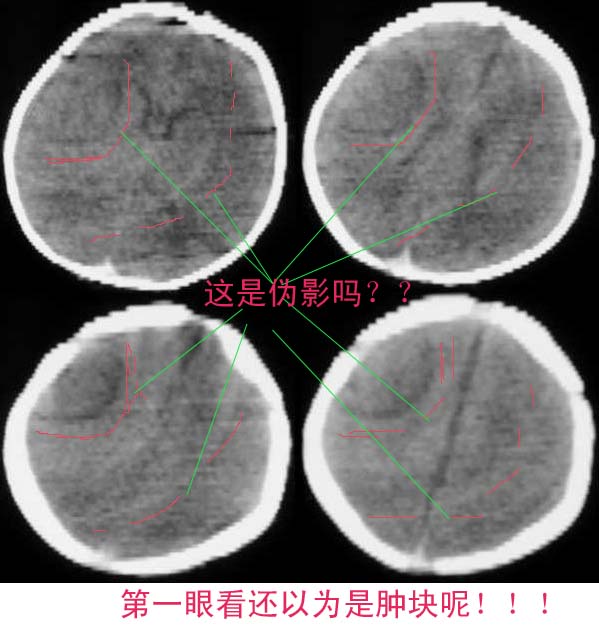

标题: CT2096:[求助]F ,3d, 因重度窒息入院余(--)。 [打印本页]

标题: CT2096:[求助]F ,3d, 因重度窒息入院余(--)。

这是什么机器做的啊伪影这么多啊,是机器造成的吗

结果:脑缺氧缺血脑病。其它的确是伪影,下午以经排除,真不好意思。幸好没误诊,谢谢分析对的战友!!

关于伪影的问题以前也讨论过。鉴别点就是机器灵敏度校正后“病变”消失;体位改变后“病变”位置随之改变。等等。